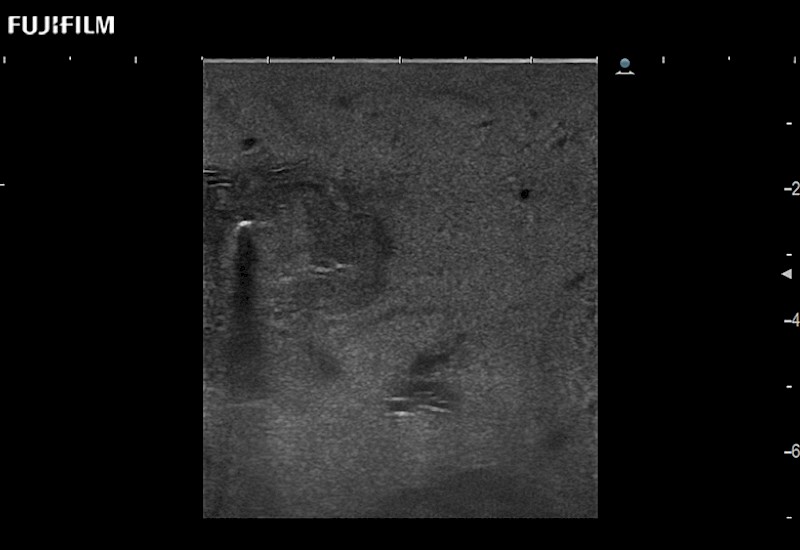

Learn moreFujifilm Healthcare continues to listen to the experts, our neurosurgeons, by developing an ultrasound system specifically designed for the Operating Room.

Guidance is the fundamental purpose for all of our surgical ultrasound technology. Fujifilm Healthcare is committed to designing tools that help neurosurgeons navigate inside the human body and provide the necessary information to immediately make critical surgical decisions.

With the ARIETTA Precision the next level of surgical ultrasound is here.